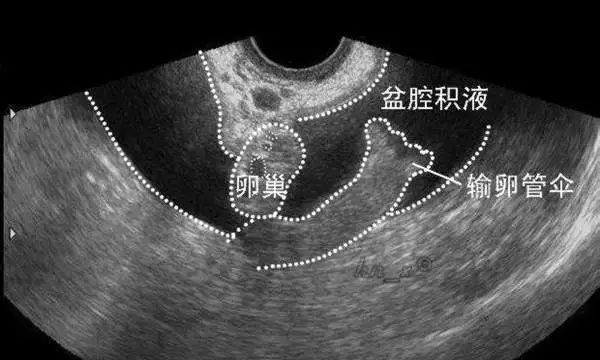

8. 盆腔积液大多不需要治疗

盆腔积液并不会引起盆腔炎、附件炎等。

平时我们看到的B超报告提示盆腔积液10-30mm,绝大多数是没有问题的。

盆腔、腹腔里的器官本来就会分泌一些液体,起到润滑和保护作用,是正常的生理表现。